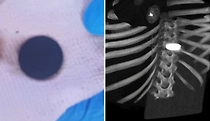

Сюрприз в желудке: У четырёхлетней россиянки во время операции на сердце нашли большую монету